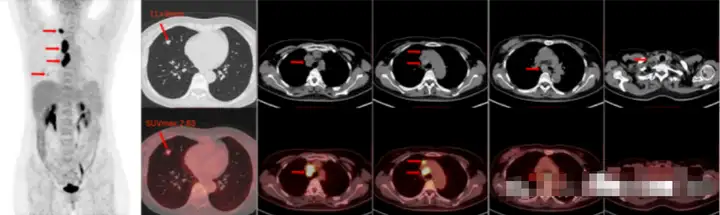

病例1

患者因胸痛就诊检查发现右肺结节,胸部CT检查显示右肺上叶尖段结节,考虑恶性肿瘤可能,预行手术治疗。然而术前的PET/CT检查提示右肺癌伴纵隔淋巴结转移及全身多发骨转移。右肺结节穿刺提示腺癌。此患者分期为IVB期,通过PET/CT避免了不必要的手术治疗。